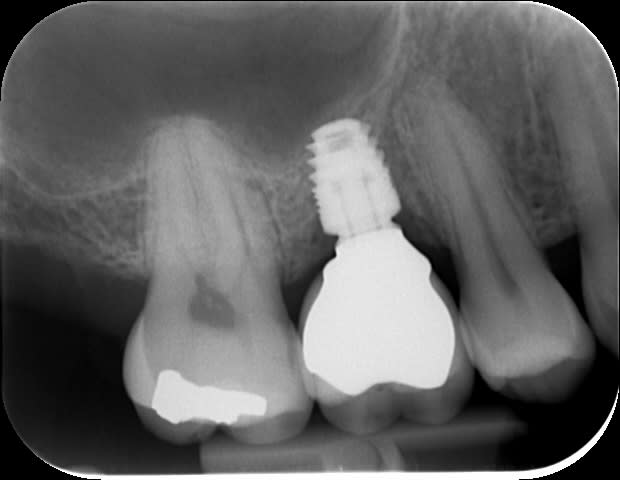

Les implants courts ça marche pas mal, ici un BICON 5x6 sur une 17 d'un confrère

Ici un ID Interactive 6mm : le jour de la pose de l'implant, à 4 mois après pose de la couronne, Bite-wing à 3 ans que je viens de faire à l'instant.

tout chaud.

5x6 mm.

Contrôle régulier du fond du puits, et après le passage du dernier foret, je sens que c'est mou en distal.

le soufflement pas le nez ne produit pas de bulle, petit bout d'éponge hémostatique pour éviter que le filetage n'accroche, et pose.

il y plus qu'attendre...

Merci des avis exprimés.

cette forme trapue avec la connectique à 1mm du nonos je trouve que ça inspire confiance.